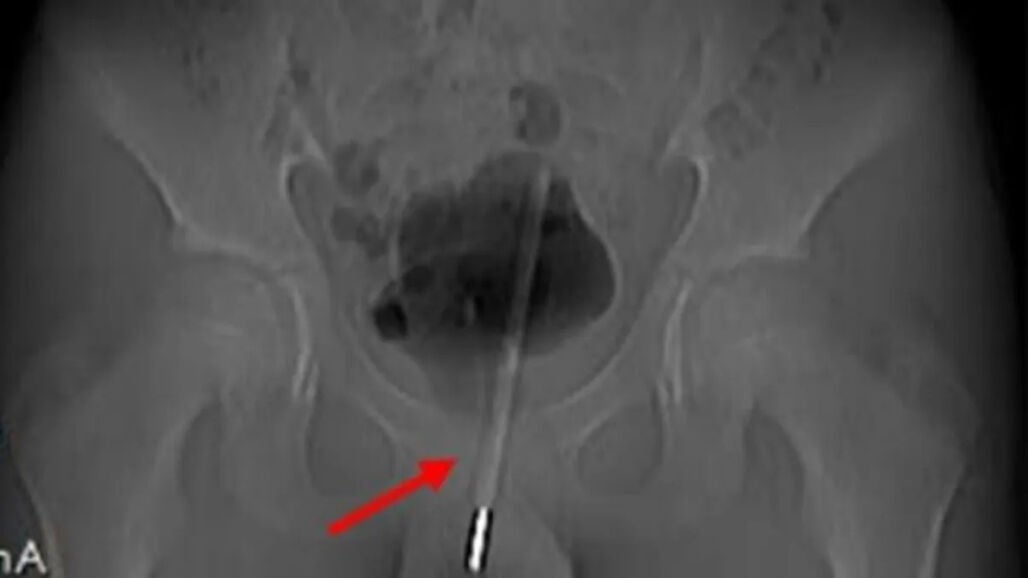

Se había introducido el termómetro por una práctica conocida como 'sondeo', con el objetivo de recibir placer sexual. En la imagen de rayos X se muestra cómo el termómetro había sido introducido hasta llegar a la vejiga del menor.

El termómetro llegó hasta la vejiga

El joven sufrió un dolor intenso hasta que fue intervenido con urgencia, pues al parecer y según revelaron los rayos X, el termómetro había sido introducido muy dentro del tracto urinario hasta llegar a la vejiga.